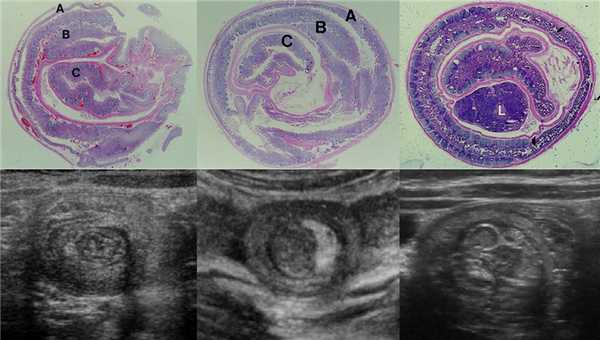

Рисунок. Кишечный инвагинат на продольном и поперечном срезах УЗИ: влагалище инвагината (А) — тонкий гипоэхогенный поясок снаружи, следом дубль висцеральной брюшины (MS) — едва заметная гиперэхогенная полоска, отечный внешний (В) и внутренний (С) цилиндры тела инвагината — гипоэхогенные кольца, которые перемежает дубль висцеральной брюшины (S) и брыжейка (М). На уровне головки инвагината (1) разделяющая полоска тонкая. По направлению к основанию инвагината из-за брыжейки разделяющая полоска становится шире, приобретает форму полумесяца (2) и даже может включать лимфоузлы (3).

Рисунок. Кишечный инвагинат имеет слоистое строение. На продольных срезах УЗИ видно «вилы» (1) или «сэндвич» (2) — три гипо- и две гиперэхогенные полосы. Внешние гипоэхогенные полосы — влагалище и наружный цилиндр тела инвагината; внутренняя гипоэхогенная полоса — внутренний цилиндр тела инвагинат; гиперэхогенные полосы — дубль висцеральной брюшины в «вилах» и брыжейка в «сэндвиче». Если брыжейка располагается только по одну сторону от внутреннего цилиндра инвагината, то на изображении «псевдопочка» (3).

Рисунок. На гистологических и УЗИ срезах можно разглядеть три кишечные петли с пятислойными стенками: вблизи головки инвагината (1); ближе к основанию инвагината (2); рядом с внутренним цилиндром попадаются лимфоузлы брыжейки (3).